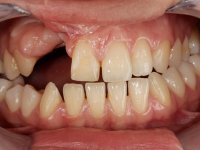

Female patient, 20 years old, non-smoker, had several surgical interventions to correct labial and palatal cleft. Patient presented a significant edentulous area between teeth 13 and 11, also due to the absence of teeth 12 and 15. Due to a traumatic impact, tooth 11 was non-vital, and extensively reconstructed with composite. Patient also had an orthodontic appliance with two prosthetic teeth and a buccal arch in this area to avoid teeth movement in this area. The area of the surgical correction of the labial and palatal cleft presented a significant deformity of hard and soft-tissues.

Root canal treatment was immediately performed on tooth 11. In the meanwhile, a CBCT scan was done to evaluate bone quality and quantity in the cleft area. The available bone was significantly reduced in vertical and horizontal dimensions. Due to the difficulty in performing a bone augmentation in this area, together with periodontal surgery to improve soft tissues, our treatment plan was the following: